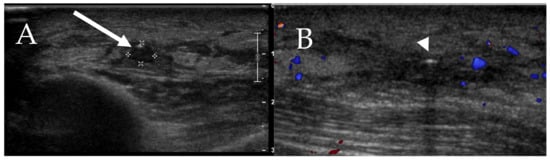

6.5. Skin